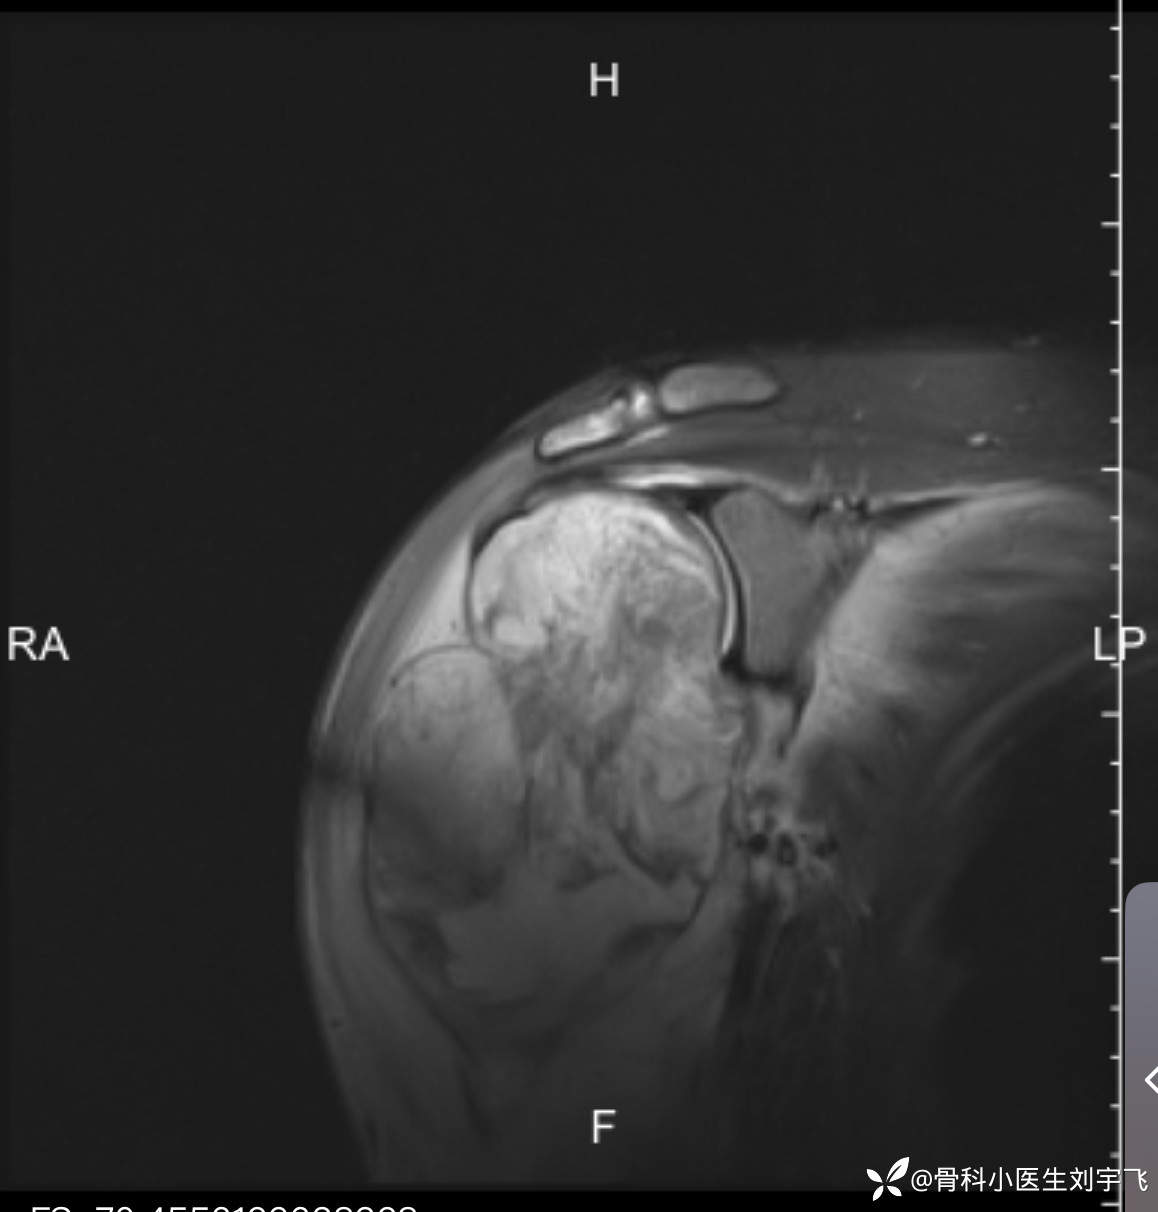

我感觉不对,理论上轻微的损伤不应该诊断肿啊,然后再次观察X线发展了问题(这时候我真想踹自己一脚)明明书上见了这么多,怎么就漏诊了,当然,我还是抱着侥幸的态度可能是良性的,继续做核磁,做了核磁,我给我的老师打了电话(知名的一位专家)老师的诊断让我心里咯噔一下,老师说骨膜反应,不像良性东西,然后我给患者建议上级医院治疗,就是找我的老师看看。

X线示:肱骨近端骨内正常骨小梁或骨皮质消失,取而代之的是密度较高的团状占位,在长骨表面可见各种异常增厚的骨膜。

骨膜反应典型的Codman三角

初步诊断骨肉瘤

建议患者进一步行MRI检查及病理活检进一步确认。